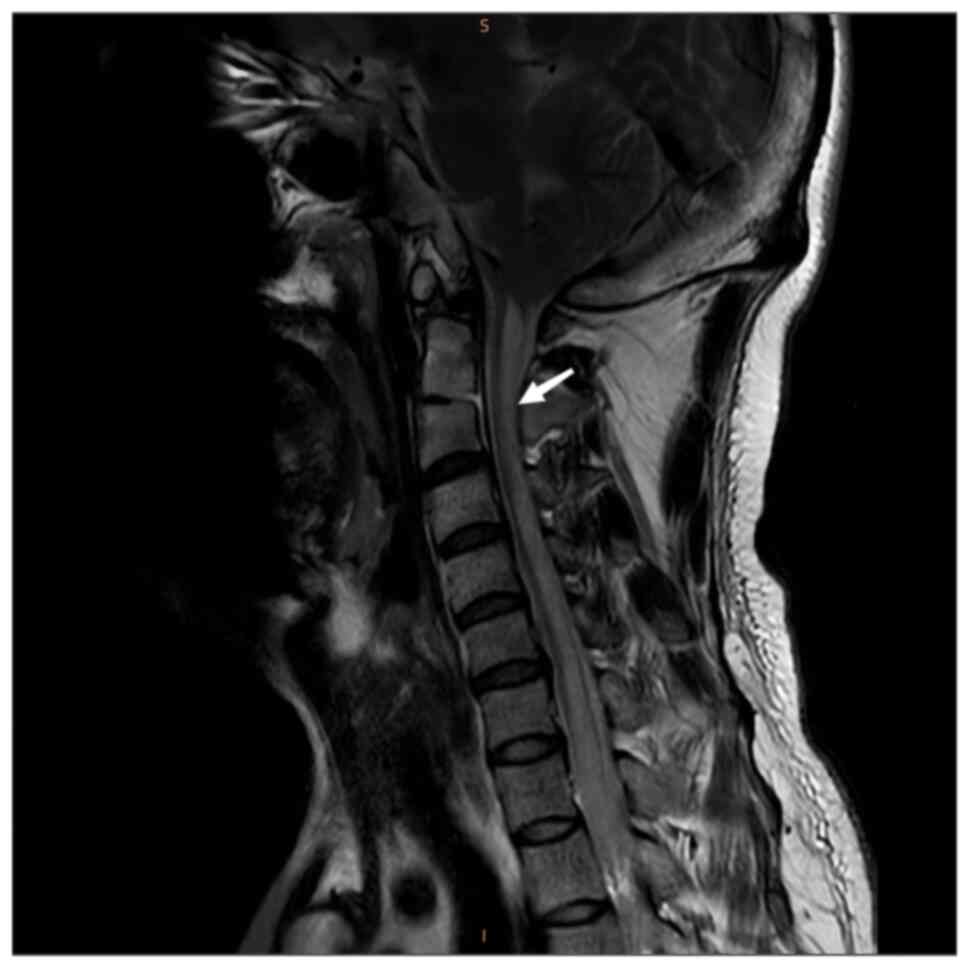

Magnetic resonance imaging (MRI) of the cervical and

thoracic spinal cord indicated an abnormal T2-weighted

intramedullary signal with a high signal (Figs. 1 and 2). Axial images indicated that the

signs were positive. SCD typically occurs in the cervical spinal

cord and the lesions usually cause a ‘figure-eight’ change in the

posterior cord.